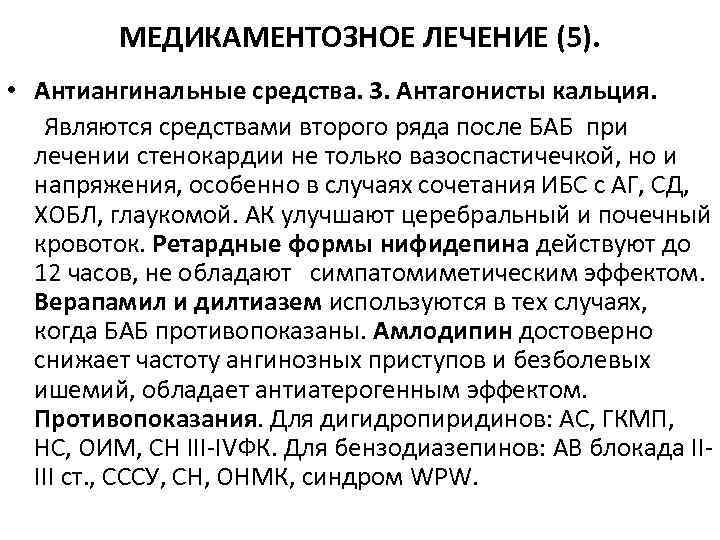

МЕДИКАМЕНТОЗНОЕ ЛЕЧЕНИЕ (5). • Антиангинальные средства. 3. Антагонисты кальция. Являются средствами второго ряда после БАБ при лечении стенокардии не только вазоспастичечкой, но и напряжения, особенно в случаях сочетания ИБС с АГ, СД, ХОБЛ, глаукомой. АК улучшают церебральный и почечный кровоток. Ретардные формы нифидепина действуют до 12 часов, не обладают симпатомиметическим эффектом. Верапамил и дилтиазем используются в тех случаях, когда БАБ противопоказаны. Амлодипин достоверно снижает частоту ангинозных приступов и безболевых ишемий, обладает антиатерогенным эффектом. Противопоказания. Для дигидропиридинов: АС, ГКМП, НС, ОИМ, СН III-IVФК. Для бензодиазепинов: АВ блокада IIIII ст. , СССУ, СН, ОНМК, синдром WPW.